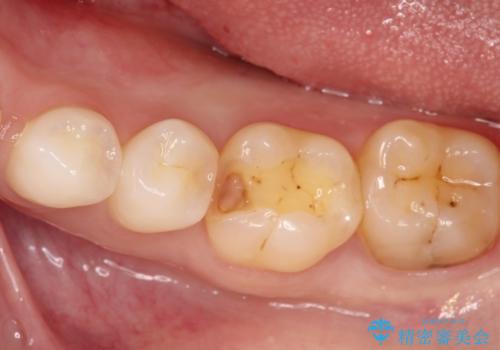

詰め物が外れた セラミックによる精密な修復

- 金属の詰め物がはずれてしまったので、精度の良いセラミックをいれたいのとのこと来院されました。

セラミックインレーにて治療することとなりました。

拡大鏡を使用して精度の高いインレーを装着しました。